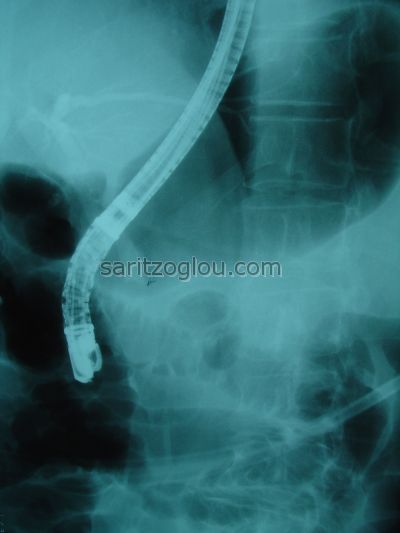

Απεικονίζεται, καθετήρας τύπου μπαλόνι με φουσκωμένο το άκρο του, καθώς εξέρχεται από τον χοληδόχο πόρο για την αφαίρεση μικρού λίθου, από το τελικό του άκρο.

Σε συνέχεια της προηγούμενης εικόνας. Το μπαλόνι εξέρχεται από τον χοληδόχο πόρο αφαιρόντας τον λίθο από το τελικό άκρο του.